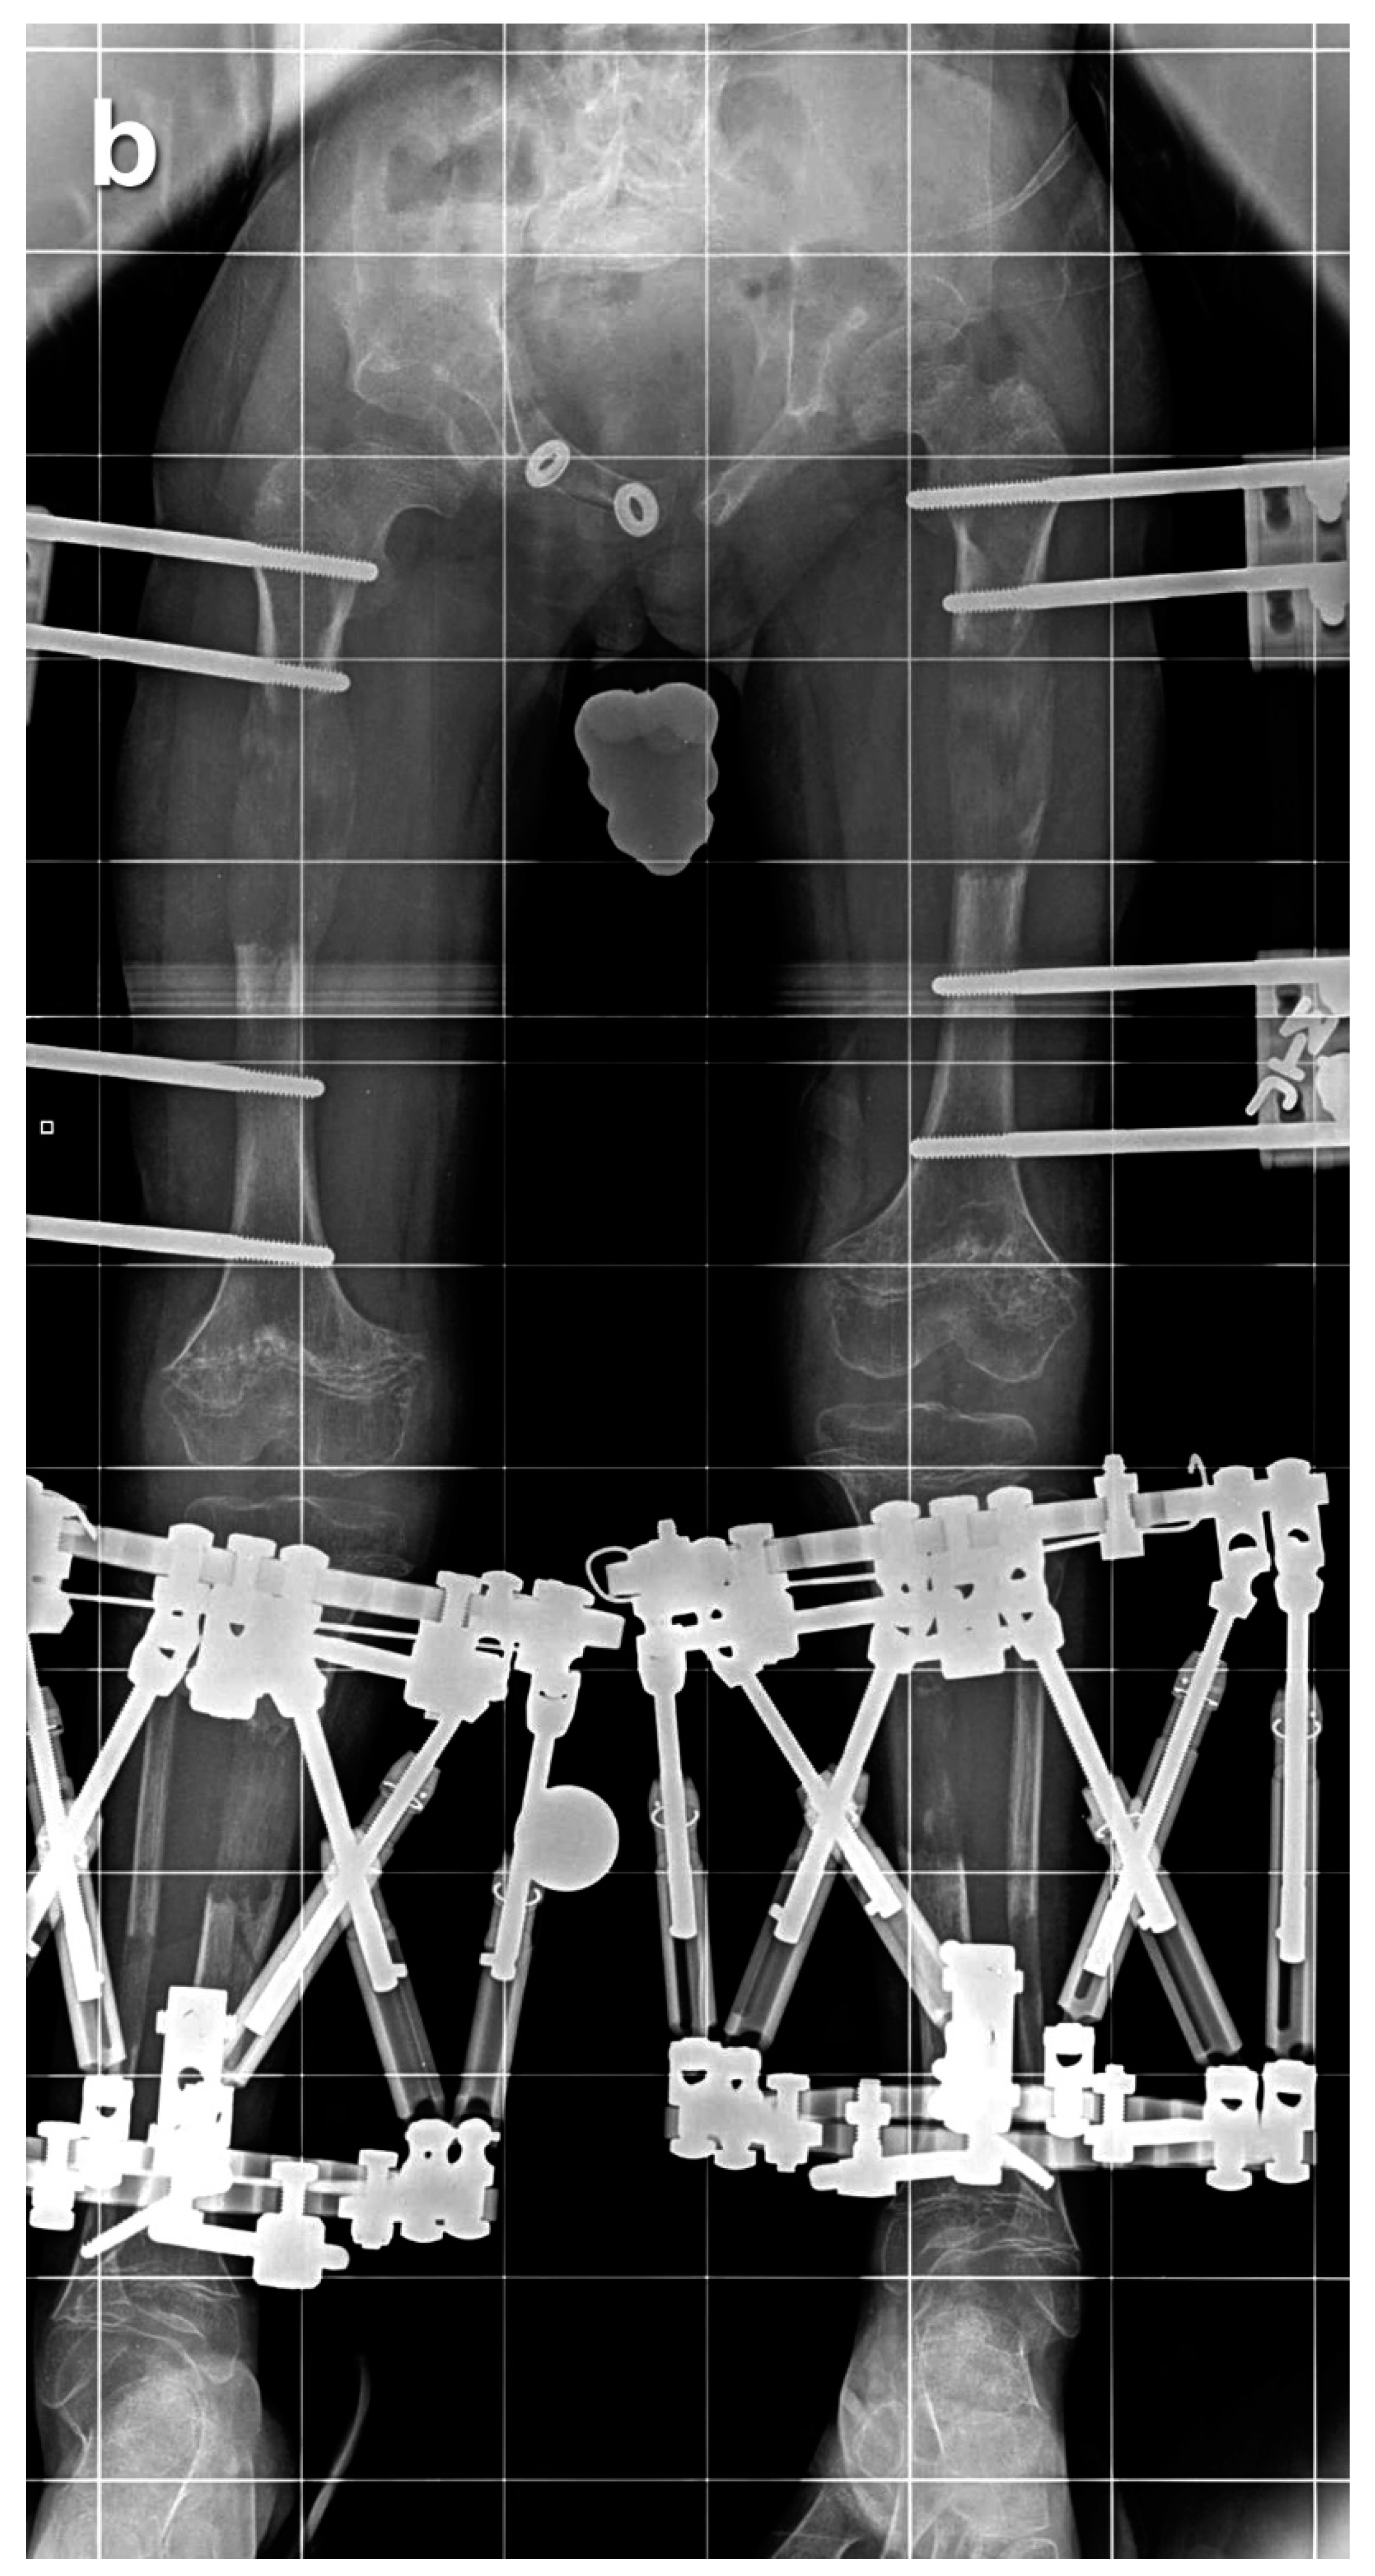

Figure 2. Eight-year-old boy who underwent two simultaneous bilateral femoral tibial lengthening (SBFTL) procedures. A Taylor Spatial Frame (Smith & Nephew, London, UK) was used for the tibia, and an Orthofix LRS (Lewisville, TX) was used for the femur. (a) Prior to first limb lengthening. (b) During first SBFTL. (c) Status after 10-cm lengthening. (d) Prior to second limb lengthening. (e) During second SBFTL. (f) Status after additional 12.5-cm lengthening (used with permission).

Of these 64 patients, nine patients were excluded as they underwent SBFTL using other methods of fixation, such as internal femoral nail or a combination of internal fixation for the femur and external fixation for the tibia. An additional five patients did not have at least 12 months of follow-up after external fixation removal and were excluded from this analysis. Fifty patients (29 males, 21 females, 200 bone segments) with achondroplasia met our inclusion criteria and underwent a total of 65 lengthening procedures (260 bone segments underwent lengthening). We defined a “procedure” as SBFTL (Figure 2).